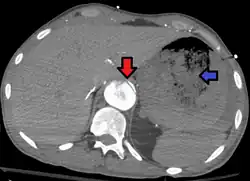

| Aorto enteric fistula and aortic dissection of the thoracic aorta. Arrow shows the flap in the aorta. Heterogeneity is blood in the stomach |